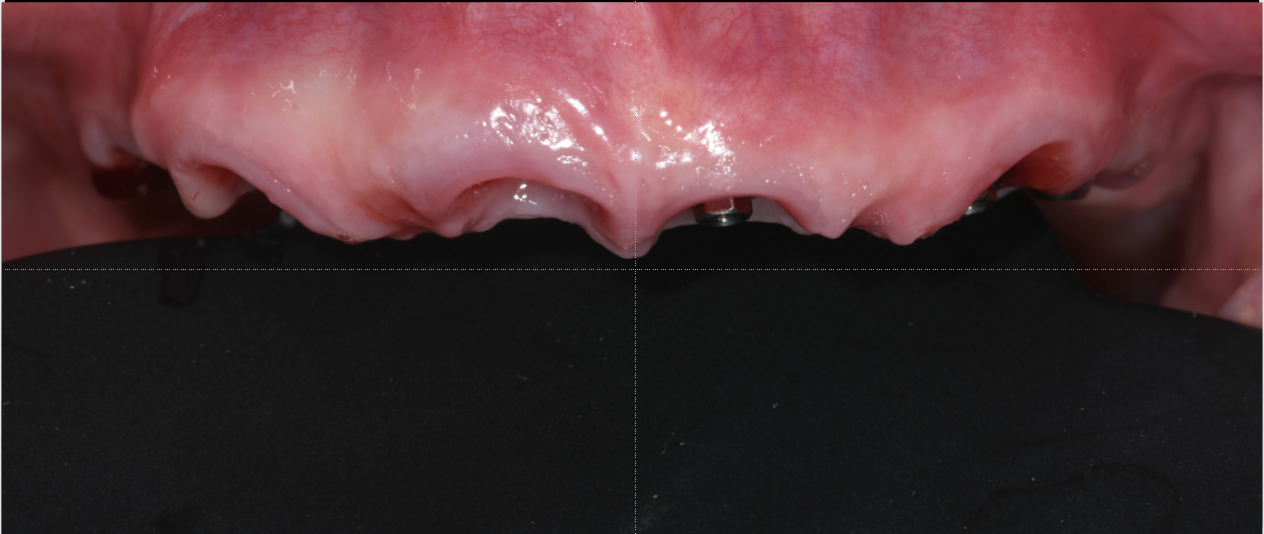

A 67-year-old female patient presented with a severely compromised anterior maxilla. Remaining teeth 13–23 showed advanced bone loss, periodontal breakdown, and a deep bite. The teeth were deemed non-restorable. The patient experienced functional limitations and significant aesthetic concern. Medical history was unremarkable.

Following the extraction of teeth 13–23, the tooth-supported guide was positioned and stabilized, allowing precise, fully guided implant surgery. Multi-Unit Abutments were inserted according to the digital plan. Immediately post-surgery, intraoral photogrammetry was performed to record the implant positions with high accuracy, eliminating the need for conventional impressions or splinting.